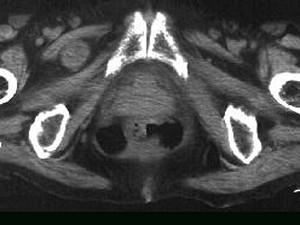

问题 女,69岁,阵发性腹痛伴恶心呕吐7h,10年前因右侧腹股沟斜疝行手术治疗,因急性肠梗阻行CT扫描如图,最可能的诊断是 ( )

选项 A、半月线疝 B、闭孔疝 C、股疝 D、腹外斜疝 E、急性肠梗阻

答案 B